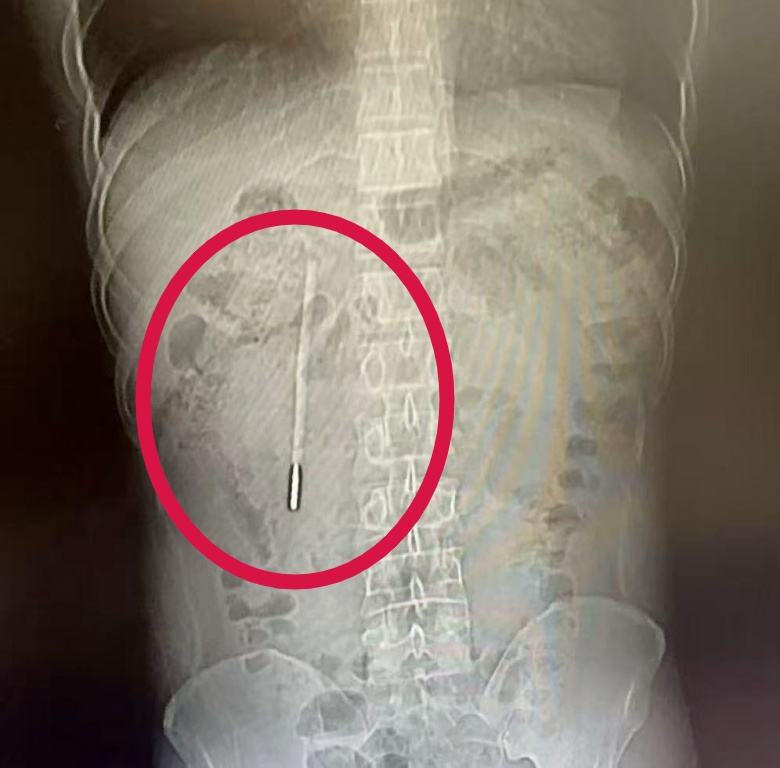

结果在CT检查中发现

其十二指肠内

竟藏有一根清晰的异物,

这根体温计在患者体内“潜伏”了整整二十年,其前端当时已抵近肠壁,存在引发穿孔、大出血等严重并发症的潜在风险。由于事发时王先生年仅12岁,因害怕没有告知家长,而家人也没有察觉到异常,此事便一直被搁置下来,直到这次腹痛就医才被发现。

体温计滞留时间极长、位置较深,且毗邻关键的胆管和胰管,操作空间十分狭窄,稍有不慎就可能导致肠壁损伤。面对这一高风险病例,温州医科大学附属第一医院龙港院区的内镜中心医护团队在相应器械辅助下精准定位,用圈套器套住体温计一端,通过缓慢轻柔的提拉,成功将整根体温计从王先生的十二指肠处取出。